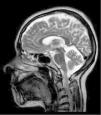

An MRI scan of the lower limbs revealed no muscle alterations, and a brain MRI scan only displayed mild cerebellar atrophy, greater than that expected given the patient's age (Fig. 1).